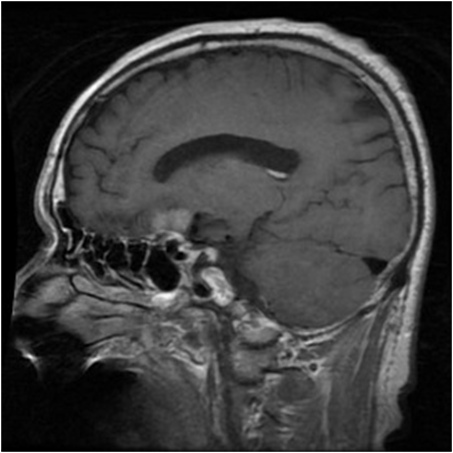

(h) CCBTM dataset

[Uncaptioned image]

Generalization from Base-to-Novel Classes

In our evaluation, we compared the proposed method against several state-of-the-art techniques, including zero-shot CLIP, and prompt learning methods like CoOp, CoCoOp, and MaPLe, thus establishing a robust benchmark for performance assessment. As depicted in Table 7(h), our method outperforms all others in all the medical image recognition datasets. For the base categories, our method demonstrates a remarkable 1.66%percent\% performance improvement. Additionally, when it comes to the novel categories, our method achieves an even more impressive 4.35%percent\% performance improvement. In terms of the harmonic mean, our method elevates the performance from the second-best at 49.45%percent\% to an outstanding 53.08%percent\%. Specifically, our approach excels in the BTMRI dataset, achieving over 3%percent\% performance improvement across all categories. Notably, it achieves a remarkable 5.53%percent\% performance improvement specifically for the novel categories. While our method may not achieve the top performance in terms of novel categories in the CHMNIST dataset, it does obtain the best performance among all prompt-learning methods. Moreover, our method continues to dominate when considering the overall performance evaluation metric, HM. Similar encouraging results are observed in the CCBTM dataset. For the base categories, our method obtains the best performance compared to all prompt-learning methods. Furthermore, the harmonic mean shows a 1.52%percent\% performance gain, further highlighting the strength and effectiveness of our proposed approach.